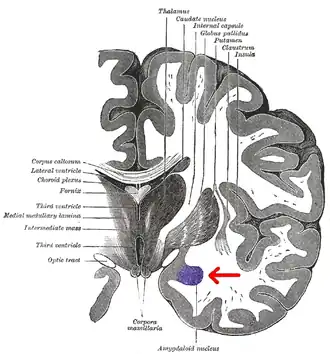

Области мозга, называемые миндалевидными ядрами, включают несколько структур со схожими функциональными характеристиками у человека и животных[7]. В число этих структур входит базолатеральный комплекс, ядра коры, срединное ядро, центральное ядро и клетки интерстиция. Базолатеральный комплекс, в свою очередь, делится на латеральное, базальное и добавочное ядра[6][8][9]. Анатомически миндалевидное тело[10], в частности, его центральное и медиальное ядра[11], иногда включаются в состав базальных ганглиев.

Миндалевидное тело посылает импульсы в гипоталамус, дорсомедиальный таламус, ретикулярное таламическое ядро, ядра тройничного и лицевого нервов, вентральной области покрышки, голубого пятна и дорсолатерального ядра покрышки[8]. Медиальное ядро вовлекается в процесс обоняния и восприятия феромонов. Оно получает информацию от обонятельной луковицы и обонятельной коры[23]. Латеральное ядро, которое посылает импульсы базолатеральному комплексу и центромедиальному ядру, получает информацию от органов чувств. Эти структуры также задействованы в возникновении эмоций у крыс и кошек[8][9][24].